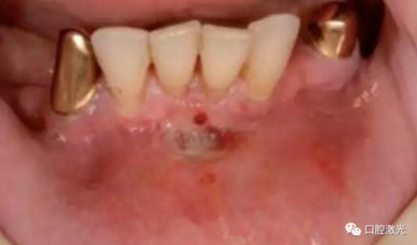

#33,#43顯示存在種植體周圍炎

激光對#43病變組織氣化切除前(左圖)后(右圖)

激光對#33病變組織氣化切除前(左圖)后(右圖)